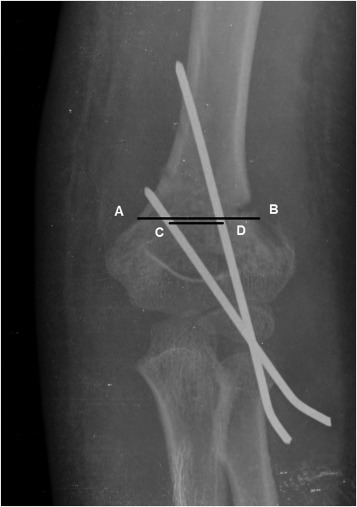

Pin-spread distance (PSD) and pin-spread ratio (PSR) at the fracture were measured using postoperative AP radiography. PSD is the measurement of the distance in the coronal plane between the pins at the fracture site (Fig. 2 ). When more than 2 pins were present, this distance was measured between the most distant pins. PSR was obtained by dividing PSD by the coronal length of the humerus at the fracture.18

Fig. 2. Pin-spread measurement at the level of the fracture. AB represents the coronal width of the humerus at the fracture site, while CD represents pin-spread distance. |